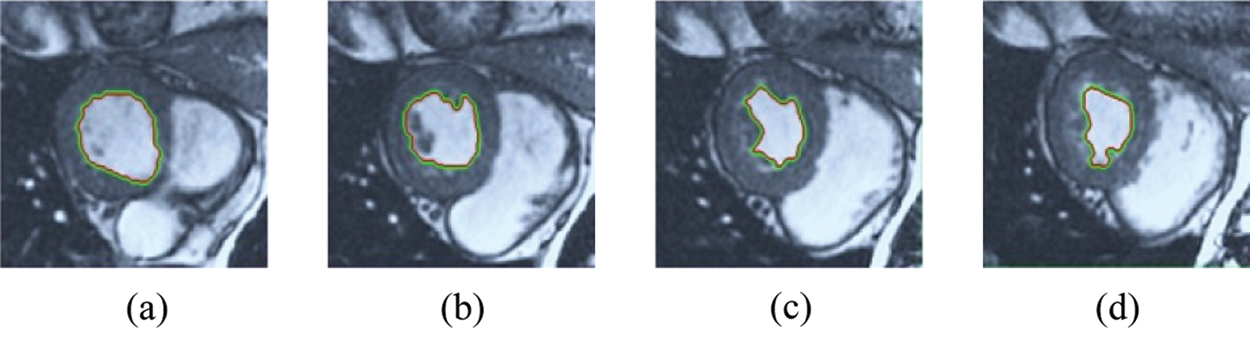

The BRW, HSRW, and ERW medical imaging segmentation schemes are executed on MATLAB, and examined on a short-axis of 3D multi-slices CMRI dataset [27]. Several segmentation performance metrics are utilized such as Dice Metric (DM), the Haussdorff distance (HS), and the Peak signal to noise ratio (PSNR). The BRW, HSRW, and ERW segmentation schemes are executed on a short-axis of 3D multi-slices CMRI datasets. The same multilayer CMRI dataset is segmented using various random walk methods. The presented results were obtained through using BRW, HSRW and ERW methods on five different groups of patients; each group contains 25 subject of multilayer CMR dataset. Experimental results illustrate that the BRW method can achieve a good segmentation of the LV cavity. The results of the HSRW algorithm have very comparable similarities to BRW, but with a slightly less efficiency and a much higher execution rate. Pre-calculations reduce the performance online time in offline mode. The average time of HSRW equals to 0.09 seconds for each slide. Raising the rate of K will improve the comparison and makes the process of segmentation more precise, but also reduces the execution time. The ERW technique results illustrate that this method has the greatest efficiency of segmentation. Figs. 5 to 7 show the resulting images of the BRW segmentation method on five sets of sample data. HSRW with pre-calculation segmentation method is applied on the same sets of sample data and illustrated in Figs. 8 to 10. Figs. 11–13 show the high efficiency segmentation using the ERW method with an earlier model for the same sets of sample data. The results of the Random Walk segmentation overcame the potential restrictions of the prior art CMR methods. The performance of segmentation is fast compared to segmentation methods based on edge and region. BRW precedes into account the properties of regions and edges, as shown in Figs. 5–7. Looking at the image as a graph, the technique makes it possible to integrate pixel relations with neighboring pixels. As a result, segmentation produces good quality BRW technique sections when their qualitative accuracy is compared to the ground truth, and this is also evident from the Tab. 1 measurements in the diastolic and systolic phases in Tab. 2 as well as in the complete cardiac cycle noticed. Figs. 8–10 illustrate the HSRW results. There are no dissimilarities observed in furthermost cases of CMR slides in the figures, but the correspondence measurements of the DM, PSNR and HS coefficients present that the results of the HSRW technique are worse than those of the BRW method. This presents that HSRW is an effective estimation of the random walk influence as mentioned in Tab. 1 and throughout the cardiac cycle in Tab. 2. The values of PSNR and DM are lower, whereas HS is higher than the BRW method, but with slight dissimilarities between HSRW and BRW methods throughout the blood circulation. The impact of execution eigenvectors pre-calculations is perfect when the execution time is faster than the BRW method and, in fact, more efficient than other segmentation method for LV heart segmentation. With the identical dataset, the ERW method shows a significant enhancement in efficiency, as presented in Figs. 11–13. From the scores, we can see that the segmentation is smoother and cleaner. The ERW method considers boundaries and areas, such as BRW, using the relations between adjacent pixels in the image. It also considers the additional regional advantage by including the assumptions that affect the results of the segmentation. Mean segmentation quality measurements are computed from the segmented images using correspondence measurements for instance DM, HS, and PSNR and verified for each method in the diastolic and systolic stages as presented in Tab. 1. Based on results, it can be determined that methods of random walk are enhanced in diastolic diagnosis and that their outcomes in the systolic stage are also of good efficiency. The results of the random walk segmentation methods in the complete blood circulation are shown in Tab. 2. The cardiac cycle similarity amounts indicate that DM and PSNR capacities of ERW are improved than the corresponding capacities in the case of the HSRW and BRW approaches; however, the HS measurements are lower than the equivalent measurements, as illustrated in Tab. 2. This designates that the ERW technique is the furthermost accurate segmentation technique among all the approaches stated above. The ERW technique has the uppermost value of PSNR, and the HSRW method has the lowermost value that denotes the uppermost speed in segmentation process.

Figure 11: ERW results for the first samples set

Figure 12: ERW results for the second samples set

Figure 13: ERW results for the third samples set